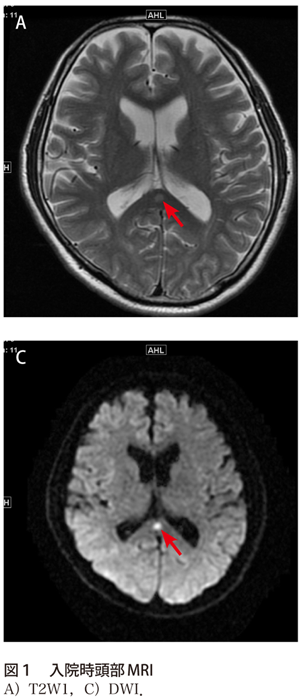

解答 解説 レジオネラ肺炎に伴う一過性の脳病変 実践 画像診断q A 羊土社 レジデントノート 羊土社